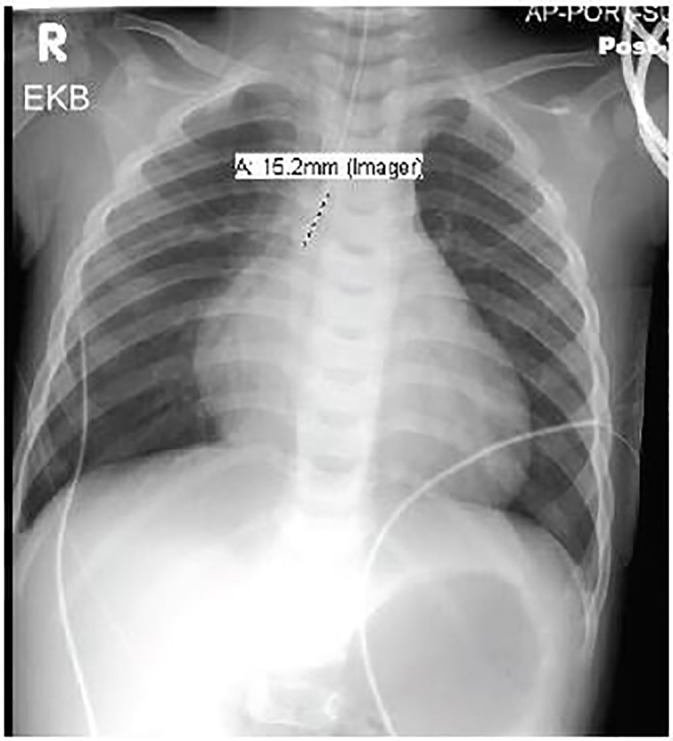

An 11-month-old male with no known past medical history presented to the ED with central nervous system (CNS) depression and then went into cardiac arrest. The patient was lethargic for two hours after awakening that morning and then had a seizure. During the prior 24–48 hours, he was irritable with decreased activity and was later retching. He was noted to be healthy before developing these symptoms. Upon arrival in the ED, he was unresponsive with no gag reflex. Vital signs were temperature 36.1° Celsius, heart rate 156 beats per minute, respiratory rate 8 breaths per minute, oxygen saturation 80% on room air. Physical exam revealed a well-nourished, 20.5 lb., 11-month-old male, with normal development, no trauma, normal oropharynx, normal tympanic membranes, no lymphadenopathy, tachycardia, clear lungs, normal abdomen and Glasgow Coma Scale rating of 4. He was intubated for significant CNS depression and required no medications for induction or paralysis. Post-intubation chest radiograph is shown in Image 2. He subsequently became bradycardic with a heart rate in the 40s with a wide complex rhythm. Initial electrocardiogram (ECG) was performed and is shown in Image 1. He then became pulseless, and cardiopulmonary resuscitation was initiated. Laboratory analysis revealed sodium 136 mmol/L, potassium 7.7 mmol/L, chloride 115 mmol/L, bicarbonate 8.0 mmol/L, blood urea nitrogen 24 mg/dL, creatinine 0.9 mg/dL, and glucose 175 mg/dL Venous blood gas pH was 6.77. An ECG was repeated (Image 3). He received intravenous fluid resuscitation, sodium bicarbonate infusion, calcium chloride, insulin, glucose, ceftriaxone and four doses of epinephrine. Resuscitation continued for approximately one hour but the patient ultimately died.